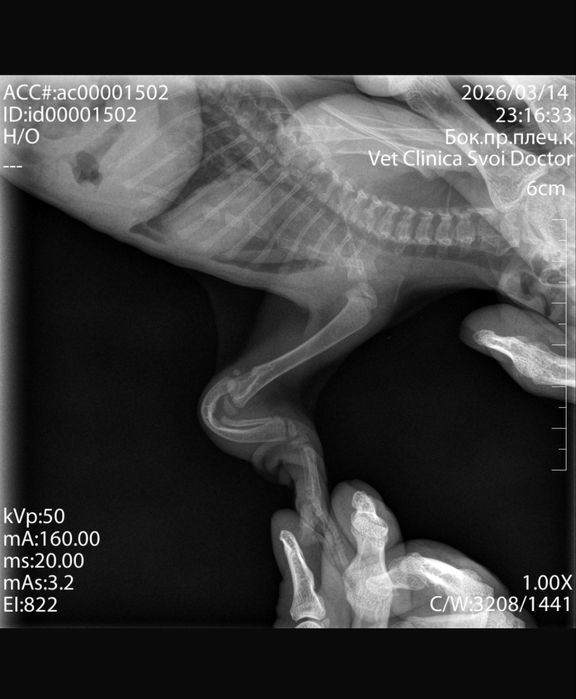

Врожденная деформация передних лап (есть рентген), поэтому хотелось бы отдать в заботливую семью